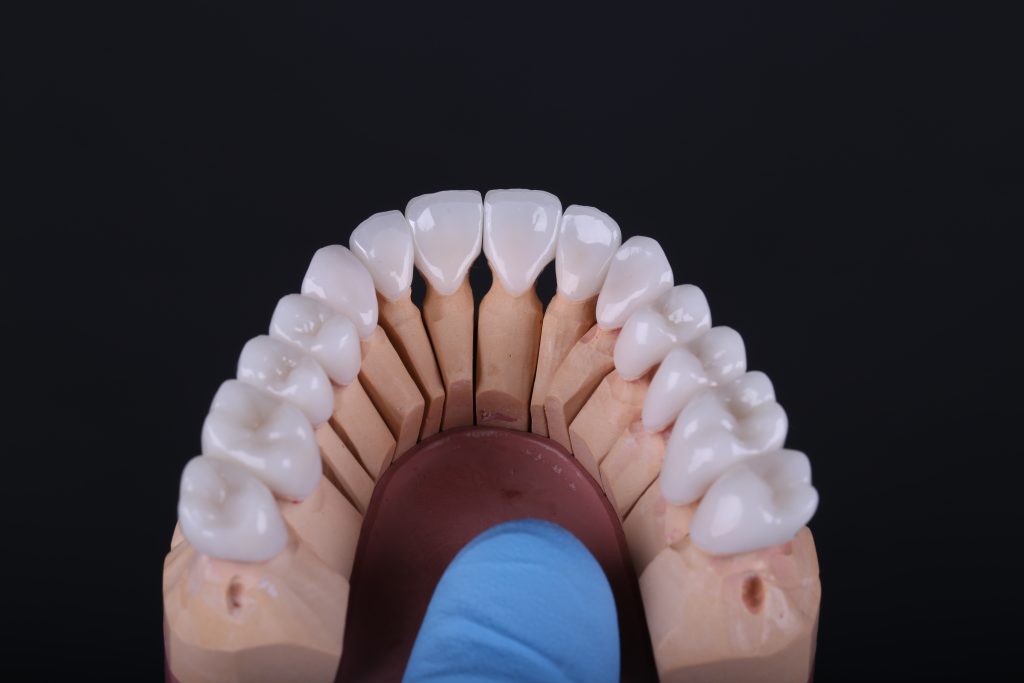

Готовые ортопедические конструкции